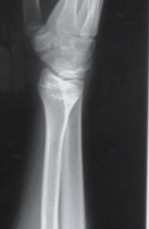

Xray